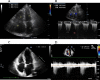

Background: Acute pulmonary embolism (APE) is often misdiagnosed as acute coronary syndrome because of the similarity of the presenting symptoms and of the electrocardiogram (ECG) manifestations. In APE, ST-segment elevation (STE) in leads V1 to V3 /V4 , mimicking anteroseptal myocardial infarction, is not a rare phenomenon. Negative T waves (NTW) in the precordial leads mimicking the "Wellens' syndrome" is an important ECG manifestation of APE. The evolution of these ECG changes-STE and NTW-in APE has not been thoroughly studied.

Methods: We present two patient cases with APE and their evolving serial ECGs to analyze the correlation between STE and NTW.

Results: NTW developed later than STE in these two patient cases.

Conclusions: NTW might represent a "postischemic" ECG pattern indicating a previous stage with transmural myocardial ischemia.